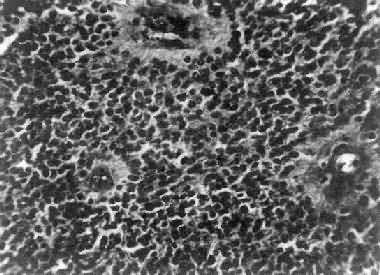

图16-25 室管膜瘤 瘤细胞为圆形或卵圆形,核染色质丰富,胞浆少,可见有细长的胞浆突起与血管相连,呈放射关,形成假菊形团 (二)髓母细胞瘤 髓母细胞瘤(medulloblastoma)好发于儿童,仅次于星形胶质细胞瘤而占第2位,其发生率占儿童颅内肿瘤的25%,发病年龄75%为15岁以下,偶见于成人,男性较女性为多(2~3:1)。 本瘤来源于小脑蚓部的原始神经上皮细胞或小脑皮质的胚胎性外颗粒层细胞,故本瘤主要见于小脑,在儿童多发生于小脑蚓部,在成人则多见于小脑半球。 肉眼观,瘤组织呈鱼肉状,色灰红。镜下,肿瘤由圆形、椭圆形或胡萝卜形细胞构成,胞核着色深,胞浆少而边界不清楚,有多少不等的核分裂像。细胞密集,间质中有纤细的纤维,血管不多。瘤细胞环绕一个嗜银性纤细的神经纤维中心作放射状排列形成典型的菊形团(图16-26),这对髓母细胞瘤的病理诊断有一定的意义。瘤细胞具有向神经元及神经胶质双向分化的潜能,既能向神经母细胞、节神经细胞分化,也能向胶质母细胞、星形胶质细胞分化。如瘤细胞侵入软脑膜,可在蛛网膜下腔脑脊液中广泛播散转移。